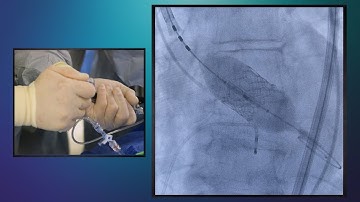

TAVR Fundamentals: Part 2